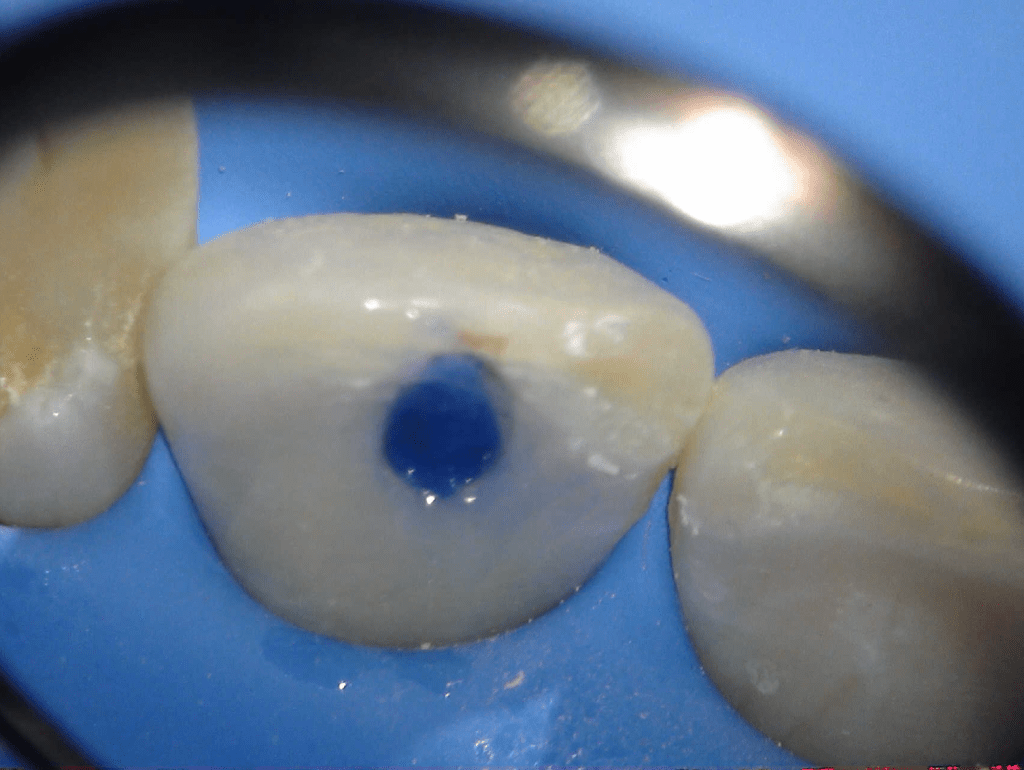

Reconstrucción preendodóntica

Molar superior

Reco palatina

Reco pared vesticular

Reco pre-endo gingivectomái, pared yuxtaosea

Reco pre-endo, molar inferior

Reco preendo + 4 conductos molar superior

Reco preendo + gingivectomía

Reco preendo, 2o Molar superior

Reconstrucción debajo de puente